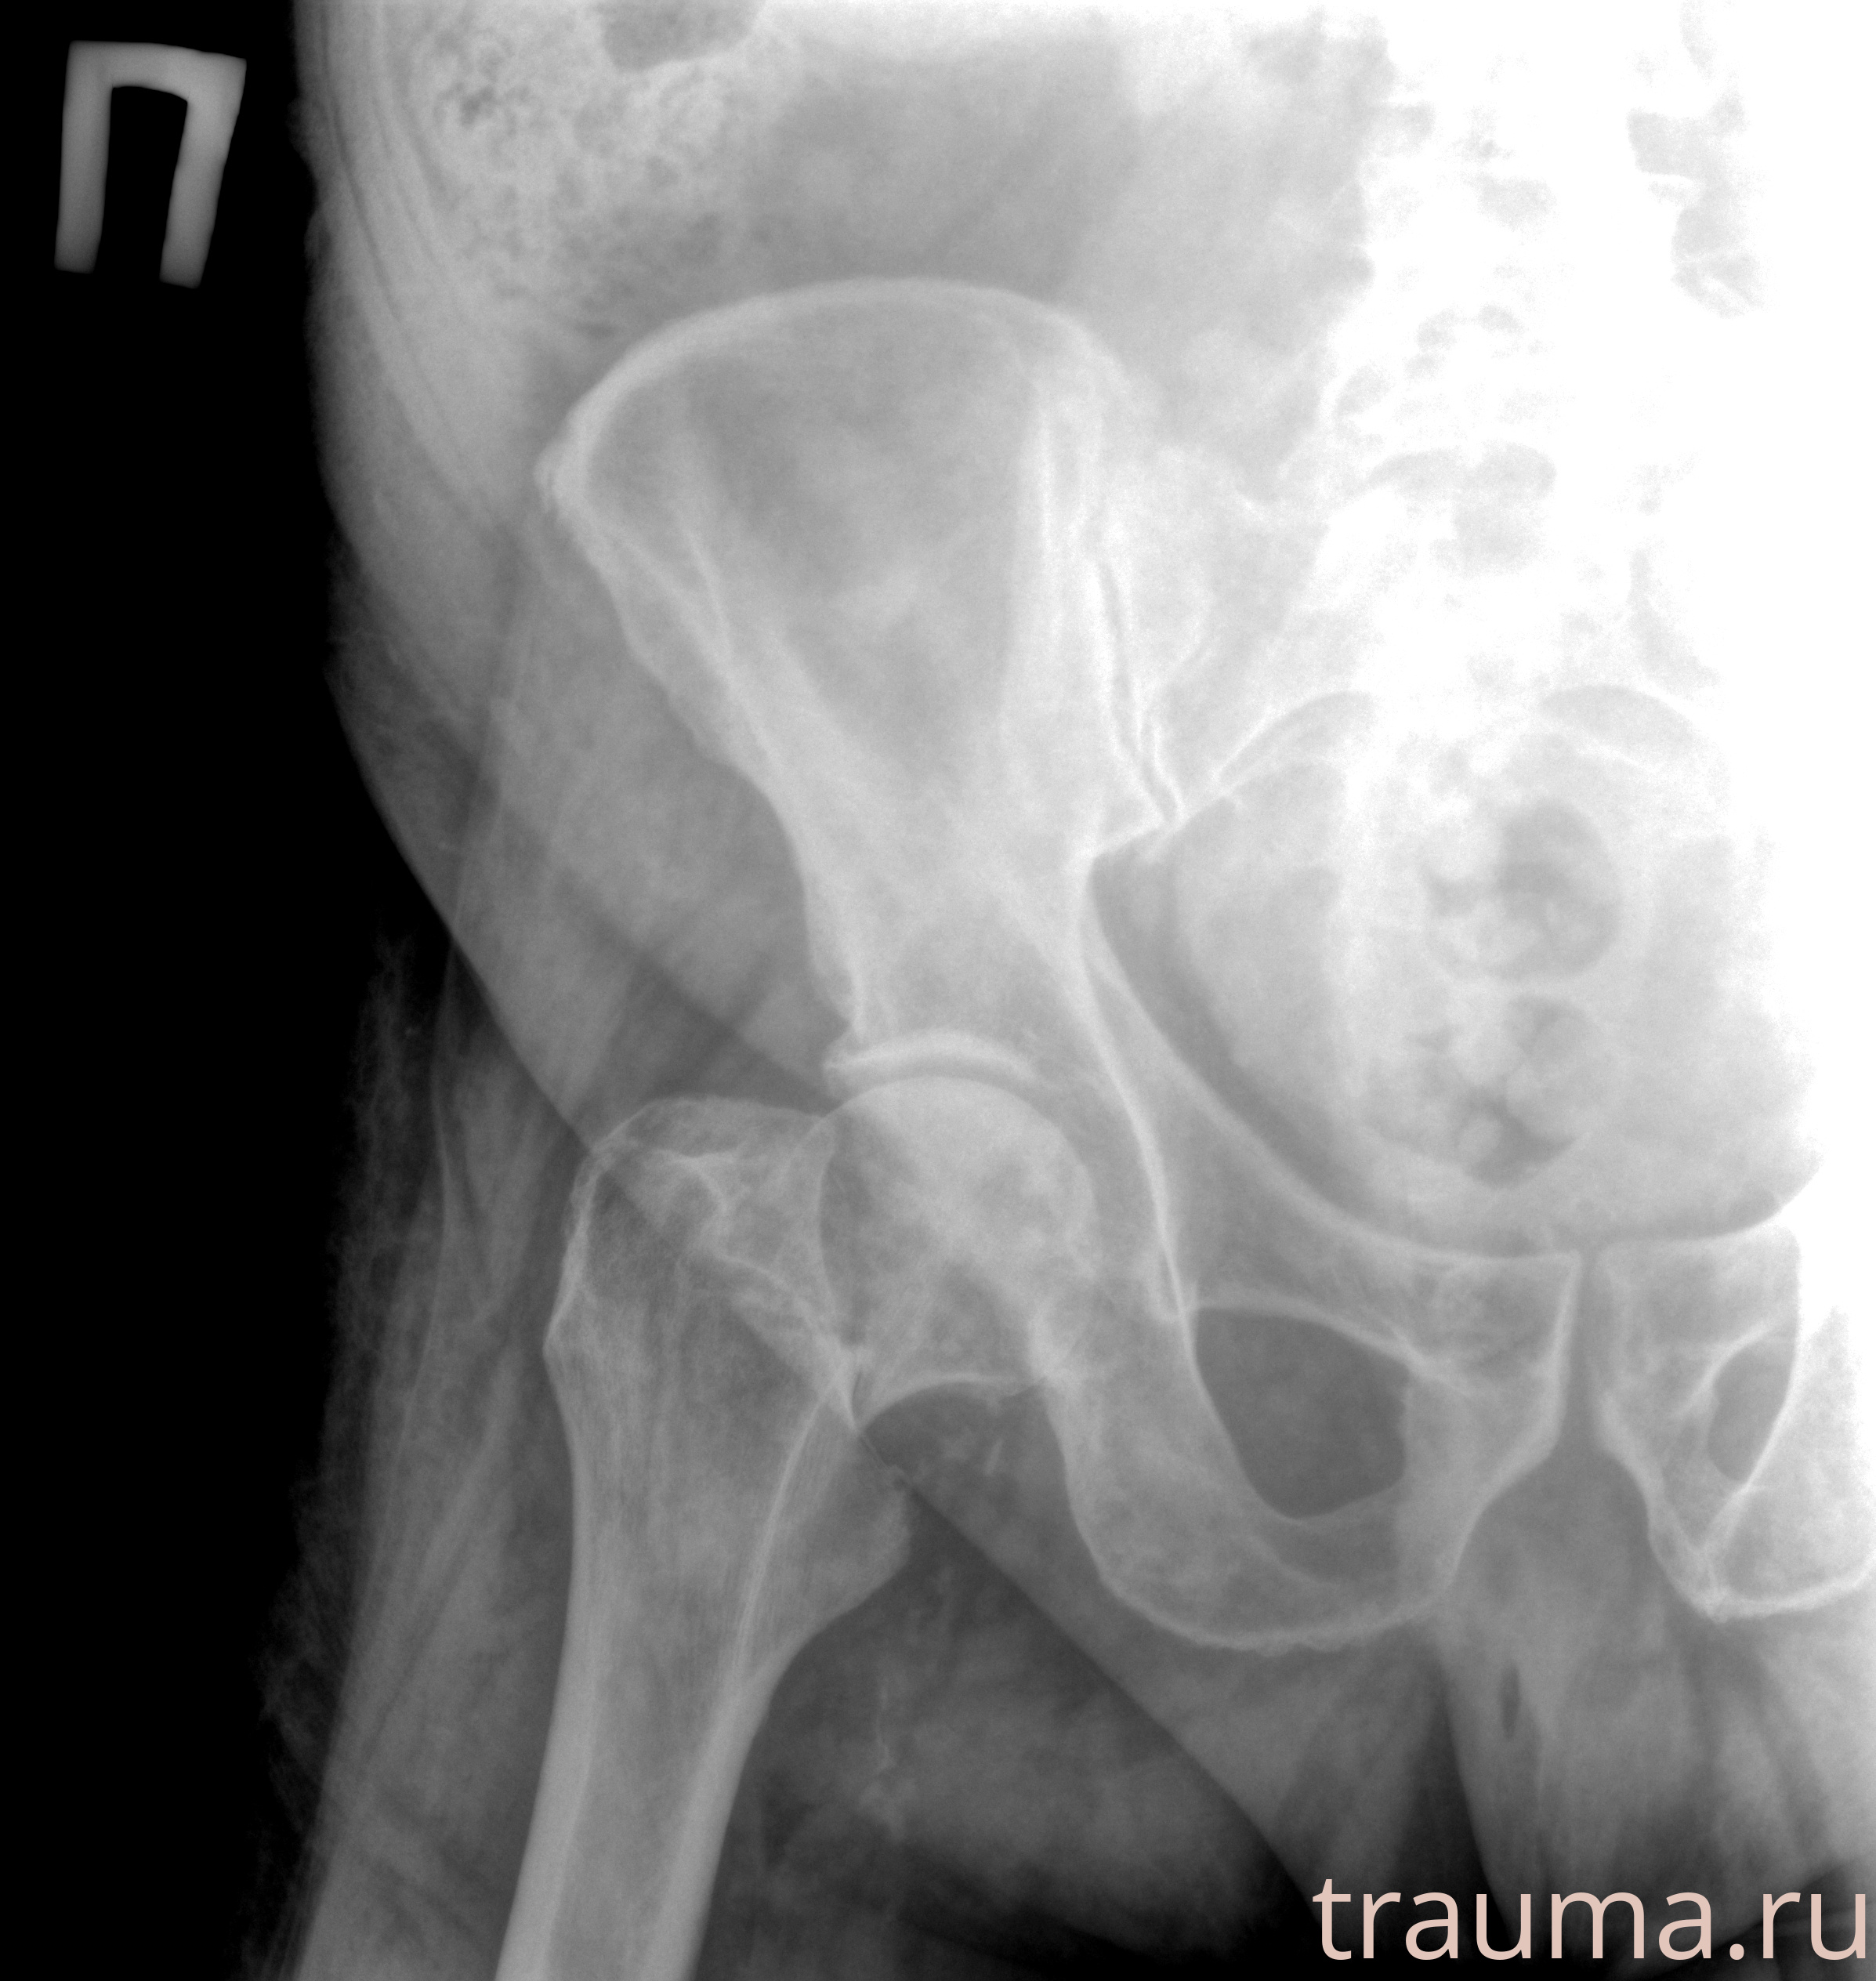

Рентгенограммы

Рентген на дому: по вашему адресу приезжает врач-рентгенолог, травматолог-ортопед с мобильным рентгеновским аппаратом, проводит диагностику травмы или заболевания, делает необходимые рентгенограммы, дает рекомендации по дальнейшему лечению. Получить качественные снимки в домашних условиях возможно благодаря уникальной методике, разработанной МосРентген Центром для института  Склифосовского